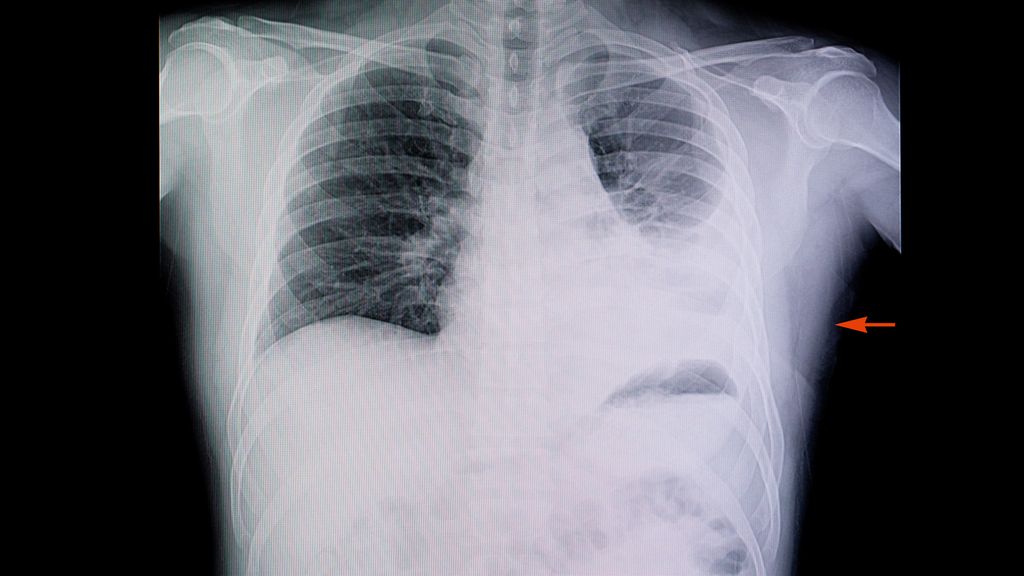

Die Empfehlungen für Diagnostik und Therapie der ambulant erworbenen Pneumonien (CAP) in den Leitlinien richten sich in erster Linie nach dem Schweregrad der Erkrankung. Während in einem ersten Schritt zwischen ambulant behandelbaren und krankenhauspflichtigen Fällen unterschieden wird, ergeben sich bei den hospitalisierten Patient:innen zwei Behandlungspfade – für die schwere und die nicht schwere CAP.

Zum Management ambulant erworbener Pneumonien (CAP) existieren zahlreiche Leitlinien mit zum Teilunterschiedlichen Empfehlungen. Dies liege daran, dass man die Erkrankung, abhängigvon der jeweiligen Fachrichtung, aus unterschiedlichen Blickwinkeln betrachten könne, führte OA Priv.-Doz. Dr. Thomas Valentin von der klinischen Abteilung für Infektiologie an der Grazer Universitätsklinik für Innere Medizin aus. Die Infectious Diseases Societyof America (IDSA) veröffentlichte 2023 einen klinischen Behandlungspfad, der auf der IDSA Guideline von 2019 basiert und online abgerufen werden kann.1 Immunsupprimierte Patienten sind in dieser Leitlinie dezidiert ausgeschlossen. Der Behandlungsalgorithmus beginnt mit der Diagnose, die auf Basis von Klinik und Bildgebung gestellt wird. Im nächsten Schritt ist die Frage zu klären, ob Hypoxie oder andere Kriterien für eine Hospitalisierung gegeben sind. Dabei können unterschiedliche Schweregrad-Scores zum Einsatz kommen. Die gebräuchlichsten sind der Pneumonia Severity Index (PSI) und der C(U)RB-65.